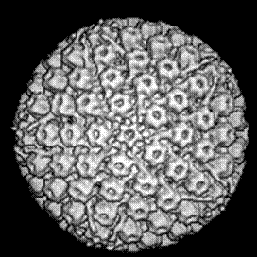

. Електронна мікрофотографія - Специфічний вигляд зараженої цітомегаловірусом клітини - «совине око».